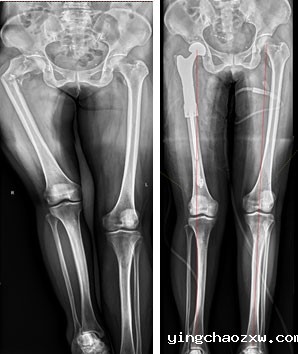

县总医院骨科团队综合研判患者病情,及时制定合理、安全、有效的治疗方案,决定为患者行右侧股骨骨肿瘤切除,肿瘤型人工髋关节置换术。因患者右股骨髓腔细小,常规人工髋关节体假体无法使用,需使用特殊假体,根据患者DR、CT,向生产厂家为患者量身定做了个性化定制型人工肿瘤髋关节假体,征对患者髓腔细,假体特别设计了个性化结合部加强套筒,确保假体强度及使用安全,术前行右下肢动脉CTA,严格评估右股骨肿瘤营养动脉血供情况,避免术中出现难以控制出血,经精心准备,在主任医师陈志强院长带领下,总医院骨科近日成功为患者实施了右侧股骨近端恶性肿瘤骨转移切除、定制肿瘤型人工髋关节置换术。手术历时2小时完成,术中患者病情平稳,术后患者疼痛疼痛消除,右下肢活动明显改善,患者的生活质量得到了极大提高,家属也十分满意。